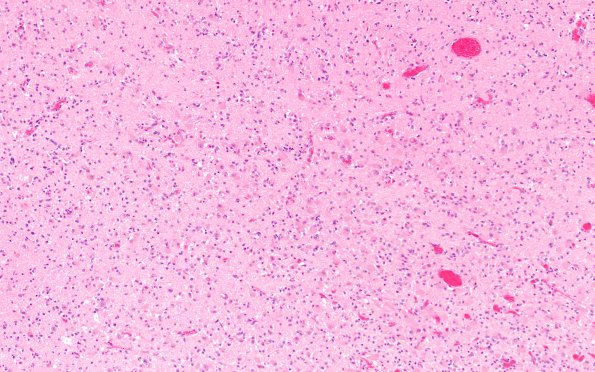

Washington University Experience | METABOLIC | Wernicke Encephalopathy | 18C6 (Case 18) Wernicke N11B H&E 10X

Higher magnification images of the MB show relatively preserved neurons, mild hemorrhage and prominent astrocytosis. (H&E)